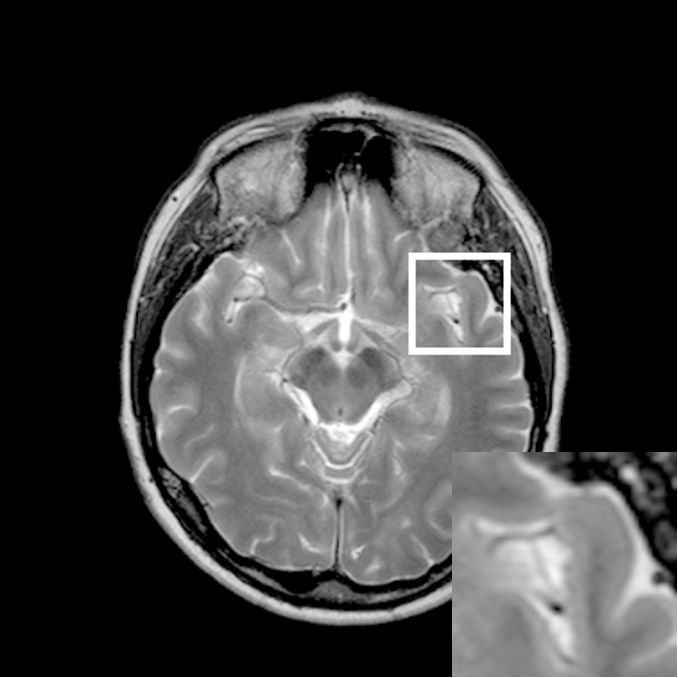

Figure 9: Reconstruction results for 30% radial sampling. (a) Original. (b)-(h) Reconstructed images. (i)-(n) The errors of six CSMRI methods.

As shown in Figs. 7, 8 and 9, Sparse MRI and DLMRI have a lot of unpleasant artifacts, Residual learning and U-net can eliminate most of artifacts, but are not ideal for restoring image details. However, the proposed method can reconstruct better MR images, which outperforms other competitive methods in visualization of structures reconstruction and artifacts removal. Meanwhile, we can see from the absolute error residuals for three sampling experiments that the proposed MDN algorithm restores a finer detail structure than other algorithms. Moreover, we present the PSNR and SSIM values in Table I for different algorithms, sampling masks and sampling rates. It is demonstrated that the proposed method provides better reconstruction performance and visual results than other competitive methods. We can also see the obvious improvement of all algorithms over zero-filling both in visualization. In particular, a higher SSIM value of Sparse MRI appears when using 30% variable density random sampling, however, Sparse MRI generates more artifacts than the proposed MDN.